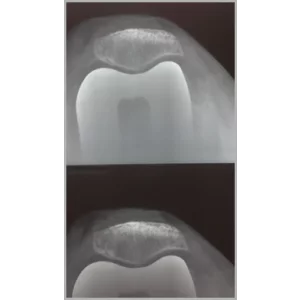

Right Total Hip Replacement And Right Total Knee Replacement In Single Stage Only